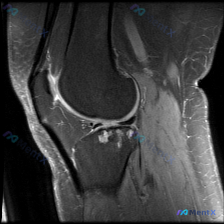

今天整理一份很有代表性的膝关节MRI读片病例,和大家分享一下思路。这个病例最初是被怀疑有半月板异常,我们一起来看看实际情况。 病例影像基本信息 这是一份膝关节MRI冠状位T2加权图像,我们先梳理所有基础观察: 1. 股骨远端、胫骨近端骨髓信号正常,没有明显骨髓水肿 2. 半月板情况:内侧半月板体部形...